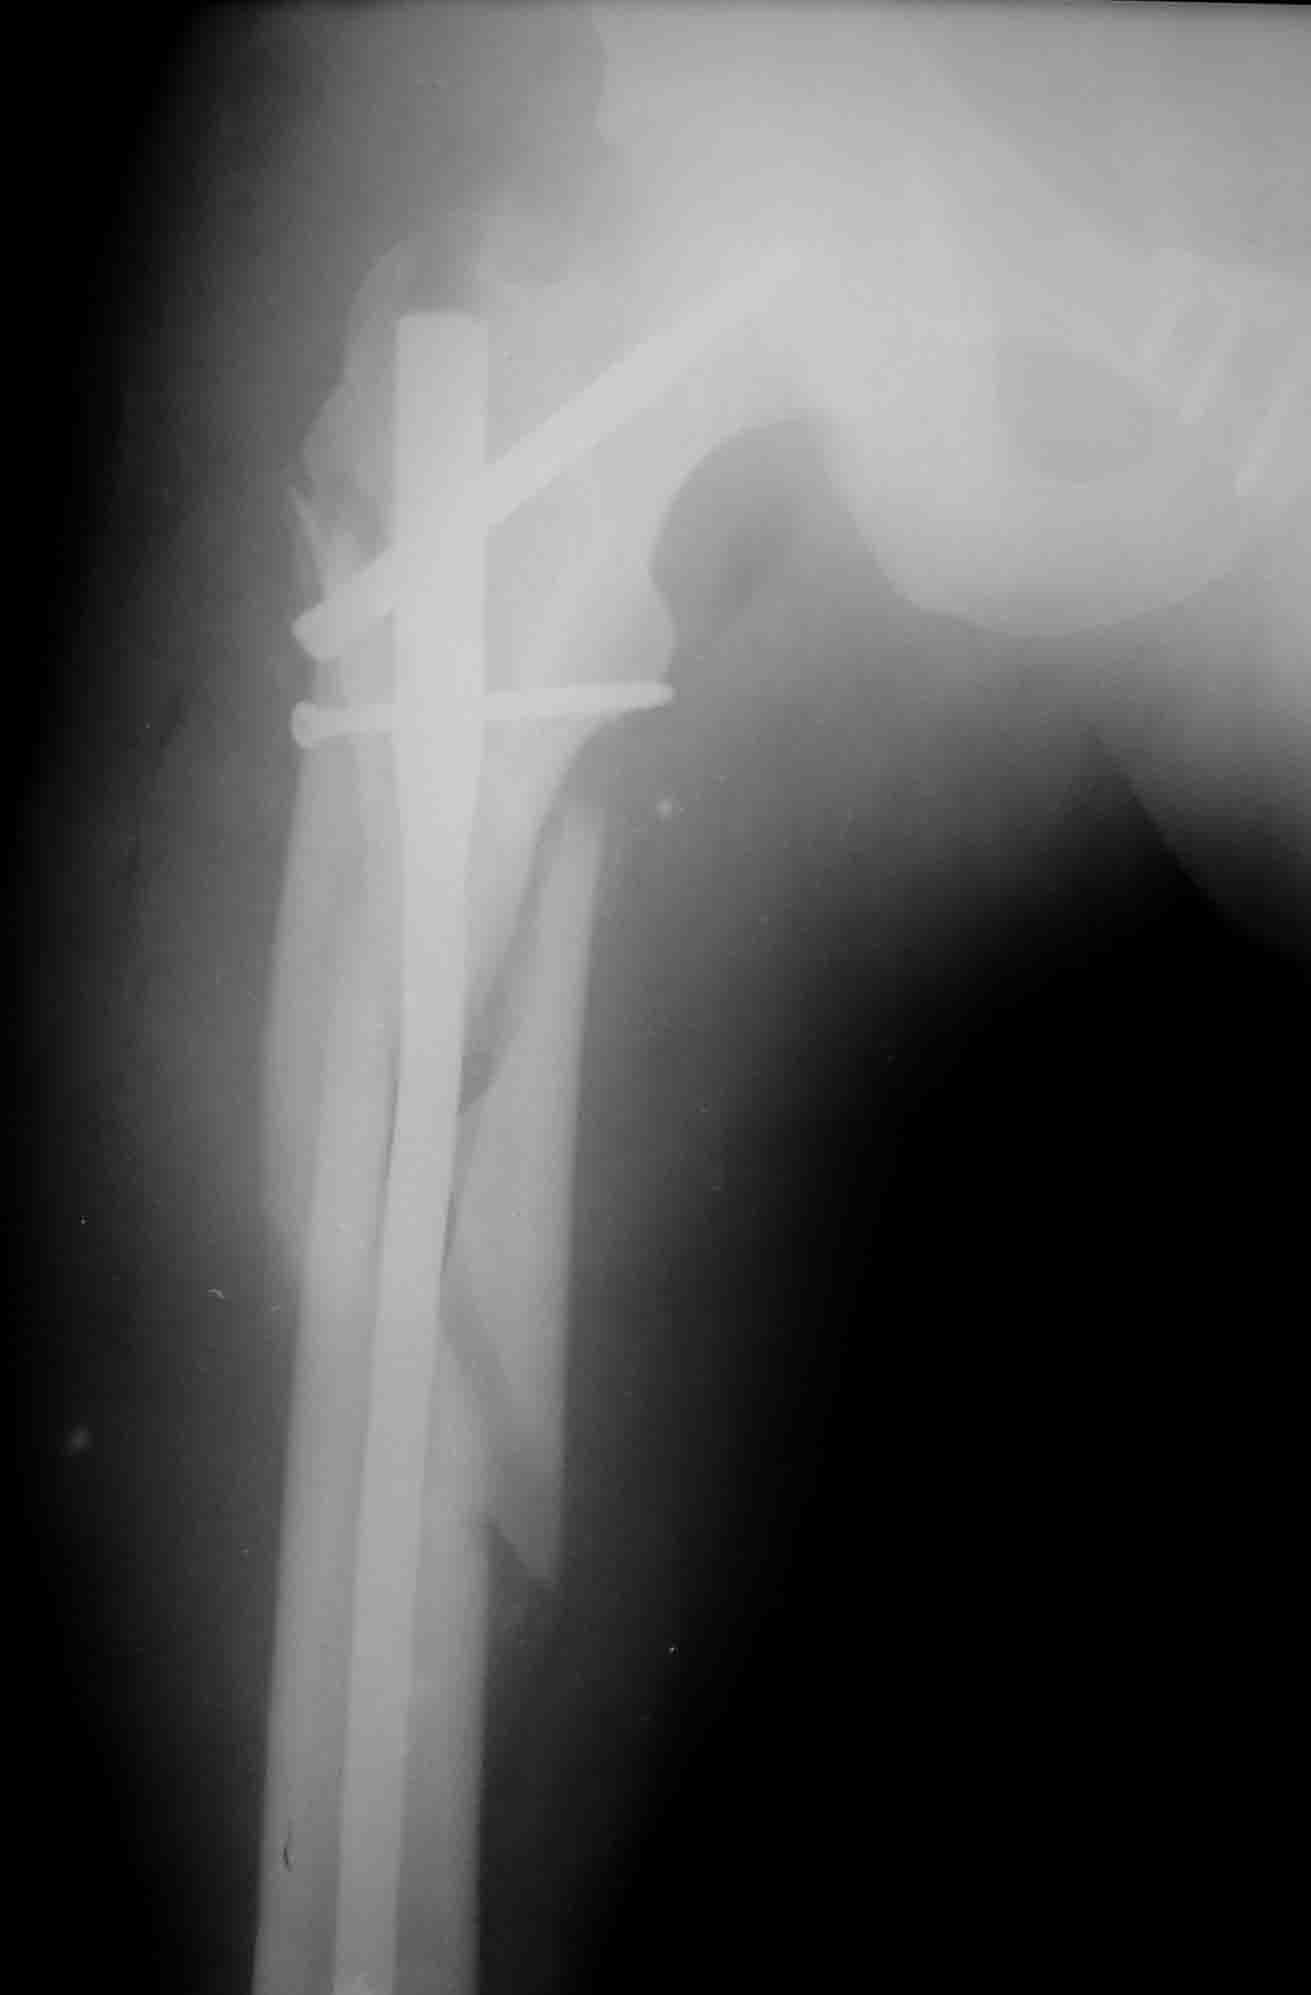

Имя     : 1.jpg

Тип     : application/octet-stream

Размер  : 45382 байтов

Описание: отсутствует

Url     : http://weborto.net:8080/pipermail/ortho/attachments/20071122/26706052/attachment-0005.obj